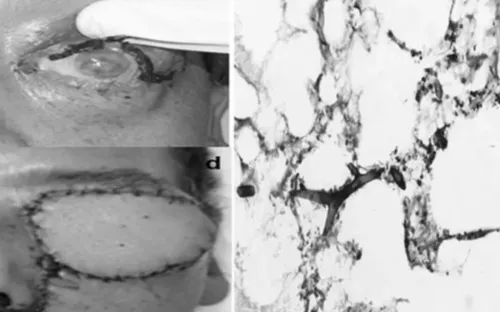

Bệnh nhân 15 tuổi tử vong do sốc phản vệ khi gây tê tủy sống

VTV.vn - Bệnh nhân 15 tuổi tại Bắc Ninh đã không qua khỏi sau khi được gây tê tủy sống để tháo dụng cụ kết hợp xương. Ngành y tế xác định đây là tai biến ngoài mong muốn.